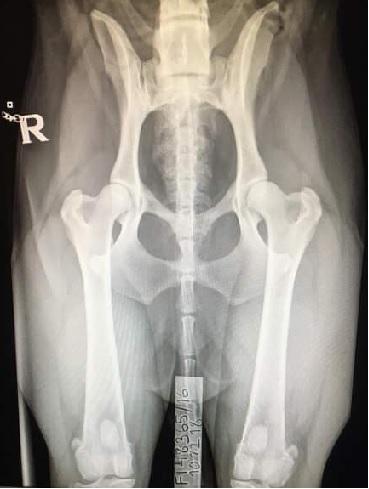

Vuosien 2015-2024 välillä syntyneistä stabijhouneista on lonkkaniveltutkittu 63 prosenttia. Tutkituista 65 prosenttia on todettu lonkiltaan terveiksi (lonkkaniveldysplasian aste A tai B) ja lieviä muutoksia (lonkkaniveldysplasian aste C) on ollut 28 prosentilla. Lopuilla (seitsemän prosenttia) koirista muutokset ovat selkeämpiä, eikä niitä PEVISAn sääntöjen mukaisesti saa käyttää jalostukseen. Huonoista lonkista johtuvaa selkeää oireilua ei ole havaittu kuin muutamalla koiralla. Lonkkien terveyteen vaikuttaa perinnöllisten tekijöiden lisäksi kasvuaikaisen ruokinnan ja liikunnan määrä ja laatu. Geneettisesti alttiilla koiralla omistaja pystyy vaikuttamaan omalla toiminnallaan jonkin verran sairauden ilmentymiseen.